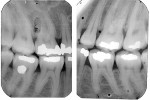

Five cases met the criteria as set forth in the study and are summarized in Table 1; radiographs of the five cases are shown in Figure 1 through Figure 21. Ages ranged from 15 to 48 years. Four patients were male and one female. All five cases involved Caucasian patients. Two cases involved the distal roots of mandibular first molars bilaterally (Figure 1, Figure 2, Figure 3, Figure 4, Figure 5, Figure 6, Figure 7, Figure 8, and Figure 18, Figure 19, Figure 20, and Figure 21); one case involved both roots of the mandibular first molars bilaterally (Figure 11, Figure 12, Figure 13, Figure 14); and two cases involved the mandibular second premolar unilaterally (Figure 9 and Figure 10, and Figure 15, Figure 16, and Figure 17). Two of the patients presented with symptoms similar to cracked-tooth syndrome (Table 1, Case 3 and Case 4), one with “chronic reversible pulpitis” (Table 1, Case 1), and two were asymptomatic (Table 1, Case 2 and Case 5).

Patients in all five cases exhibited PARR of the involved roots, as previously described (Figure 1 through Figure 21).40 The roots showed shortening and blunting of the apex of greater than 2 mm in all five cases. In three of the five cases, the PARR self-arrested without any treatment. The mandibular left first molar in Case 1 (Figure 5, Figure 6, Figure 7, and Figure 8) received conventional root canal therapy (RCT), while the mandibular right first molar in Case 3 (Figure 11, Figure 12, Figure 13, Figure 14) received a bonded ceramic crown. The PARR appears to have arrested in these two cases, and the outcome of the treatment in relation to the resorption could not be determined. The symptoms the patients were experiencing did eventually resolve. Consequently, all five study cases became symptom-free, including the patient who received conventional RCT (Case 1).

The Case 1 patient, who was the son of the Case 2 patient, was observed in preoperative orthodontic records prior to initiating orthodontic therapy (Figure 1 and Figure 2). The Case 1 patient also demonstrated PARR of the mandibular anterior incisors post-orthodontic therapy (Figure 8). The Case 5 patient had serial extractions completed as a child, but no fixed or removable orthodontic appliances were utilized. Past medical histories were all noncontributory (Table 1). No cases of MICR or MIAR were identified in any of the files reviewed.

The radiologic feature of PARR is characteristic of LIAR. PARR was readily apparent in all five cases (Figure 1 through Figure 21). Two or more millimeters of apical root were resorbed and replaced with normal-appearing trabeculated bone. The PDL space and remnants of the lamina dura appeared to be intact. The apical root canal space appeared patent but somewhat narrowed. The teeth were not ankylosed. Conversely, PARR due to trauma results in ankylosis with bone replacement resorption from both the apical and lateral directions of the root with obliteration of the root canal space and PDL space.1,40-42 PARR from orthodontics would be impossible to distinguish from LIAR radiographically; however, a history of prior orthodontics and the location of the involved teeth would separate this process from LIAR (Table 2).